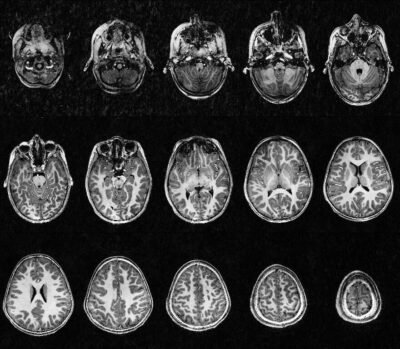

Pour la première fois en France, des images du cerveau d’un enfant de 6 ans ont été obtenues grâce à une IRM à 7 teslas (IRM 7T), au sein de NeuroSpin (CEA Joliot). Cette prouesse technologique, réalisée avec la participation de l’Institut Robert Debré du Cerveau de l’Enfant, marque une avancée majeure dans l’étude du cerveau en développement et des troubles du neurodéveloppement.

L’IRM à 7 teslas est une technologie d’imagerie ultra-haut champ, qui permet d’obtenir une résolution et un contraste bien supérieurs à ceux des IRM classiques (1,5 ou 3T), utilisées couramment à l’hôpital.

Une première mondiale chez l’enfant

Jusqu’à récemment, cette technologie était réservée aux adultes, en raison des défis techniques et réglementaires liés à la sécurité des jeunes patients. Après plusieurs années de recherche et développement, les équipes du CEA NeuroSpin ont :